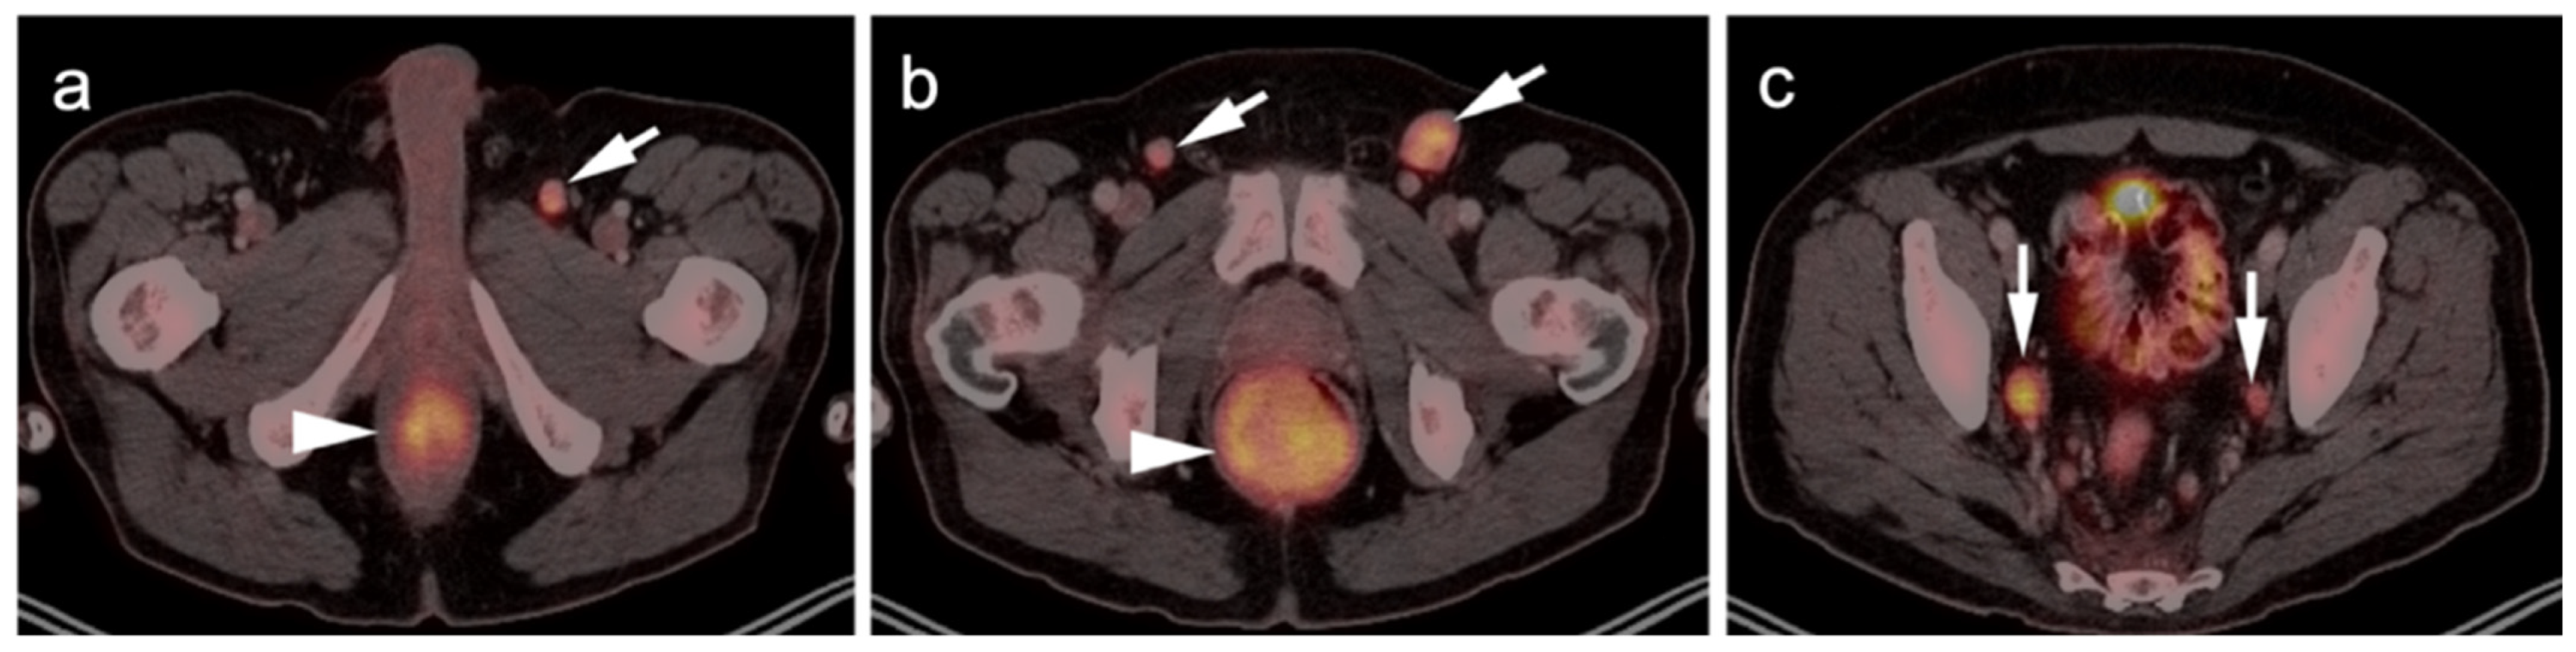

2.3.3. Mucosal Melanoma